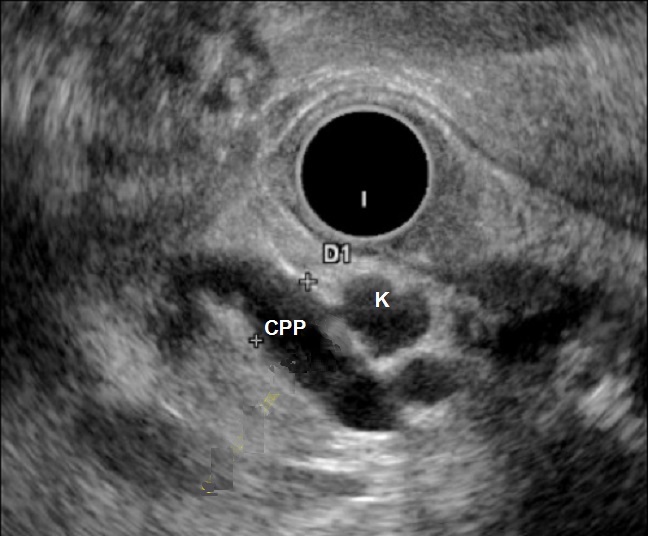

Image endo-echographie d'une

TIPMP avec des kystes aechogene a bord fine et etre communication

avec le canal pancreatique principale hypoechogene

tres dilate |